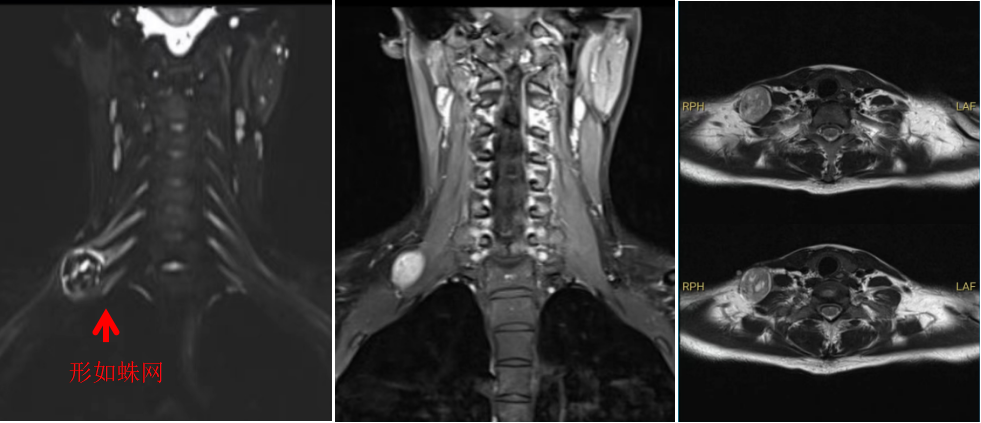

图1

手术由林飞跃医生主刀,团队医生相互配合。由于王女士的肿瘤生长于颈部重要神经丛之中,就宛如盘踞在“蜘蛛网”上(图1),给手术带来了巨大的挑战。医生们如同在一片错综复杂的神经网络中寻找出路,每一步操作都需要格外谨慎,生怕触碰到任何一根关键的神经纤维。林医生一点点地将肿瘤与周围的神经组织分离,经过近两个小时的紧张手术,将肿瘤完整切除。术后,王女士上肢功能恢复完好。

林飞跃医生介绍,臂丛神经鞘瘤临床表现以颈肩部肿块、Tinel征、感觉症状为主,严重时甚至会出现神经支配的上肢肌力减退。发生在臂丛下干的神经鞘瘤,若向下生长,需与肺尖肿瘤或转移性肿瘤进行鉴别,除了常规的病史及体格检查外,MRI检查被认为是显示臂丛神经及其疾病较好的影像学检查方法。手术切除是治疗臂丛神经鞘瘤的有效方法,特别适用于出现神经压迫症状的患者。手术技巧尤为关键,体现在暴露肿瘤、分离包绕肿瘤的神经束等方面。手术过程中神经有可能因牵拉而出现术后功能障碍,但这种损伤是可逆的,经过保守治疗可恢复。